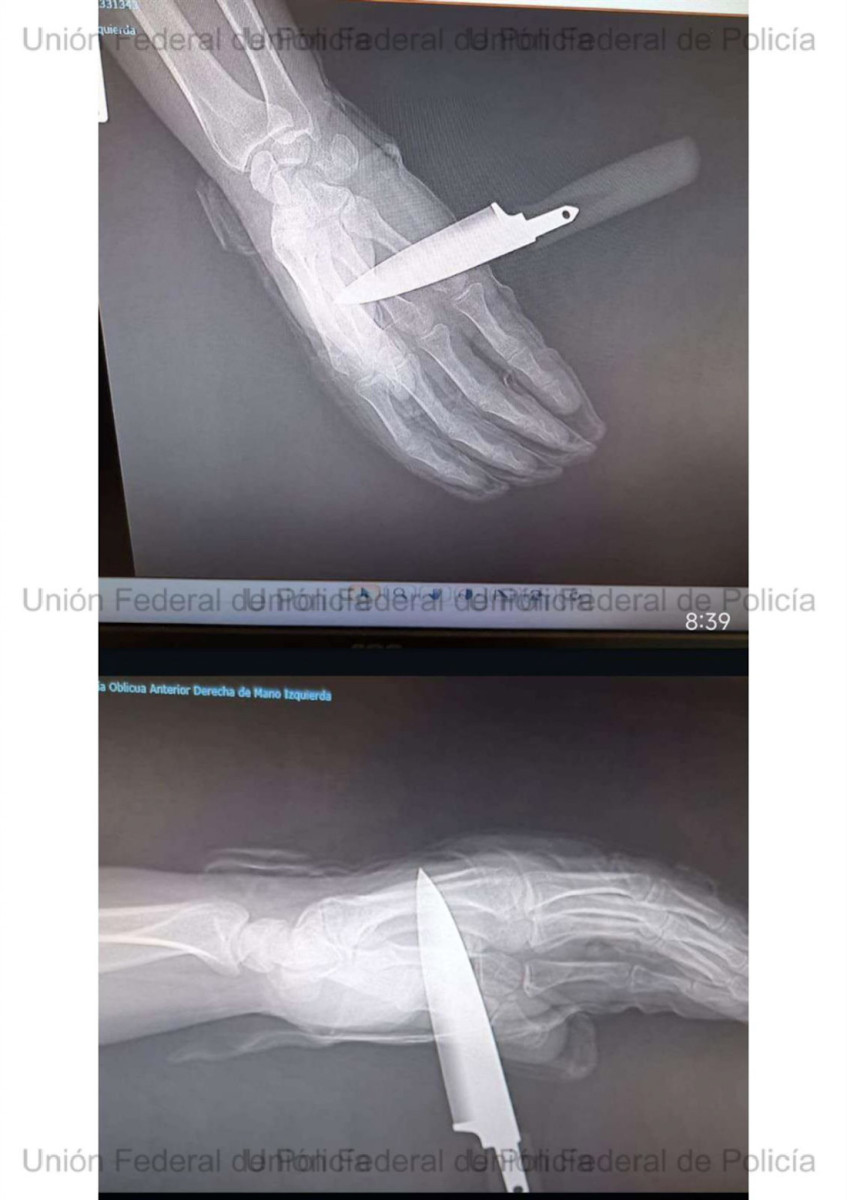

El colectivo policial ha destacado que el chaleco antibalas fue determinante para salvarle la vida, evitando que la agresión tuviera consecuencias fatales. Posteriormente, el atacante intentó asestar una segunda puñalada que el agente logró repeler parcialmente, aunque el arma blanca llegó a atravesarle la mano.

El agente herido tuvo que ser atendido en un centro hospitalario, al que acudió con el cuchillo aún clavado. Desde la UFP han mostrado su “total apoyo” al compañero y han anunciado que solicitarán para él el ingreso en la Orden del Mérito Policial con distintivo rojo en reconocimiento a su actuación.